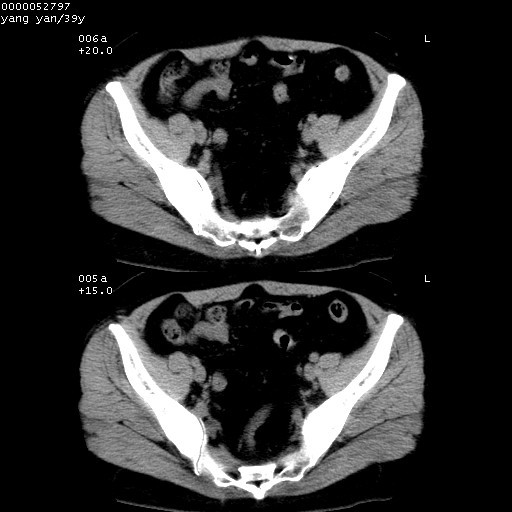

患者 女,39岁。因外伤检查,偶然发现。

典型!双侧骶髂关节致密性骨炎。

病变累及髂骨关节面,腰椎椎小关节结构紊乱,不除外强直性脊柱炎,建议结合实验室检查

典型!病变主要累及双侧髂骨。常见于育龄期妇女。

髂骨致密性骨炎系一种以骨质硬化为特点的非特异性炎症,有高度致密的骨硬化现象,尤其以髂骨下2/3更为明显,但关节间隙则无改变。因位于骶髂关节,且该关节症状明显,故又称之为“骶髂关节致密性骨炎”。 本病90%以上为中年女性,以妊娠后期、尤其分娩后为多见,亦可见于尿路或女性附件慢性感染后,或盆腔内其他感染。此外,臀骶部的外伤亦可诱发或引起本病。  妊娠、分娩及外伤均可引起骶髂关节韧带的撕裂而易使局部的血供受阻。因此早期局部呈现充血、水肿及渗出增加等,渐而局部出现增生与变性反应,随着胶原纤维的致密化而向硬化演变;血管形成厚壁血管,易闭塞而引起髂骨耳状面处缺血和缺氧,骨质呈现硬化性改变,以致手术时局部出血较少。骶髂关节囊壁显示纤维增生、弹性降低及松动样改变。继发于盆腔内炎症者亦出现相类似的病理改变,可能系细菌内毒素作用所致。